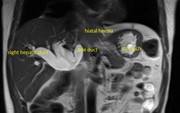

Intestinal obstruction secondary to left paraduodenal hernia

John R. Gusz and Lauren M. Wright

Journal of Surgical Case Reports, Volume 2015, Issue 7, July 2015, rjv090, https://doi.org/10.1093/jscr/rjv090